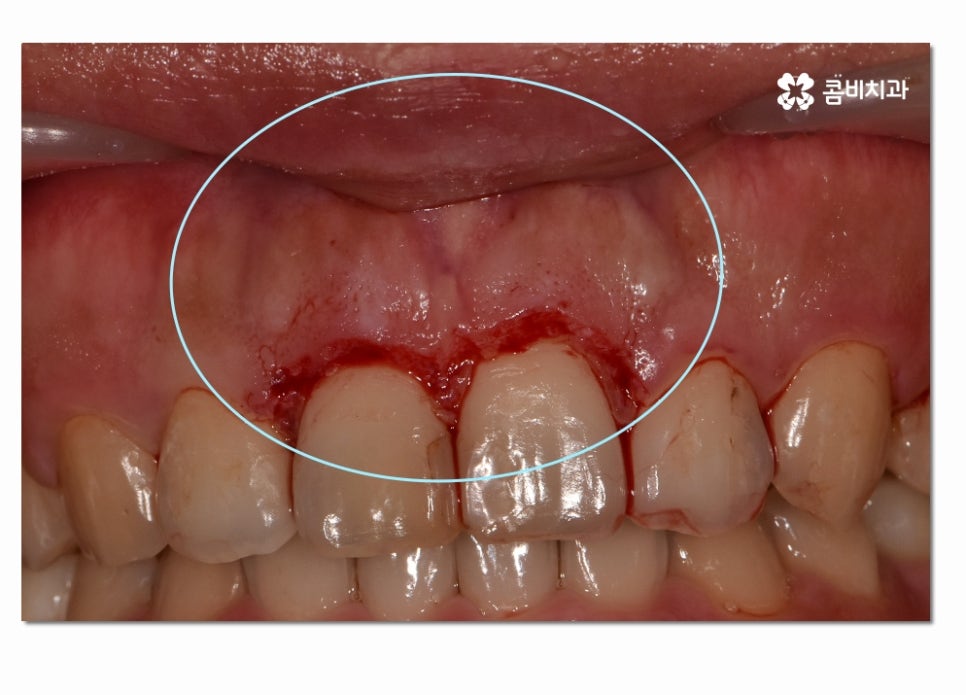

이러한 수술적인 방법은 잇몸을 절개하고 치은 깊숙하게 숨어 있는

치석을 제거해 주거나 치주조직이 다시 건강하게

회복될 수 있도록 형태를 바꿔주며 재생을 돕는 방법이라 할 수 있는데요.

위에 보시는 것처럼 치은절제술 치료가 잘 이뤄지고 잇몸이 다시

건강한 색과 모양으로 회복된 것을 느낄 수 있는데요.

본 글은 콤비치과의 의료광고 포스팅이며

개인에 따라 출혈 및 부작용이 발생할 수 있습니다.